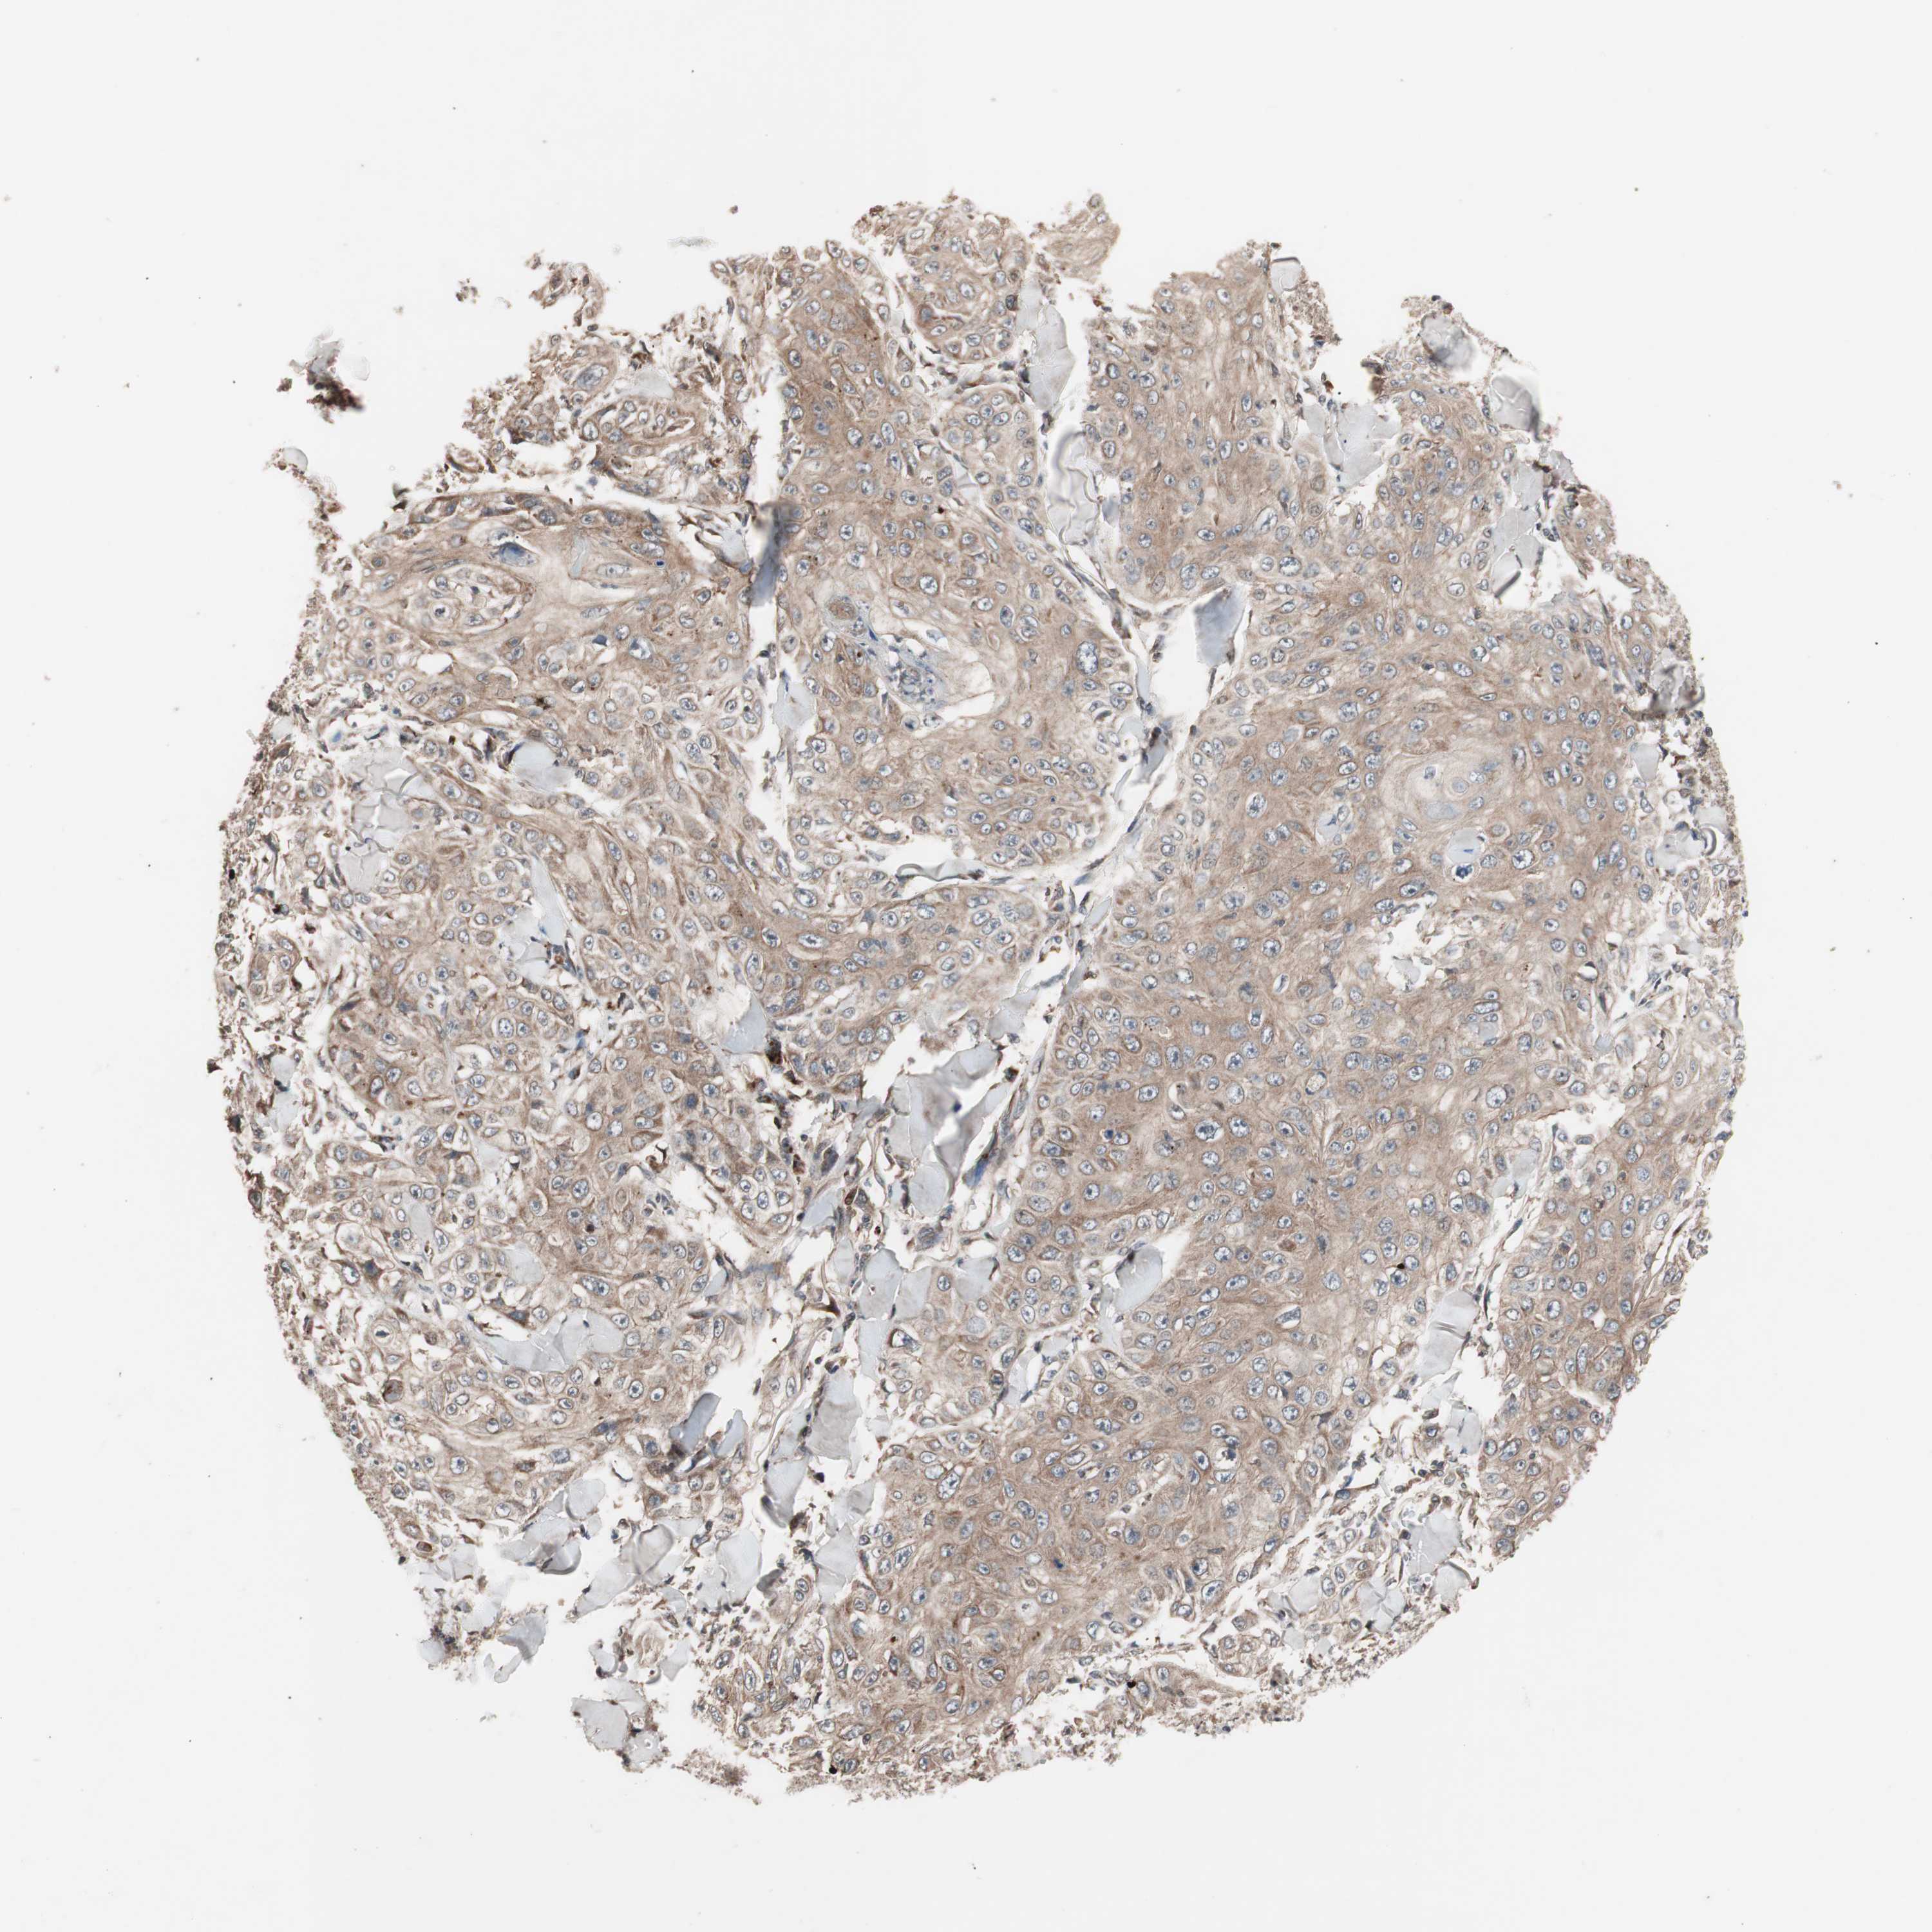

SKIN CANCER - Protein expressioni

A mouse-over function shows sample information and annotation data. Click on an image to view it in a full screen mode. Samples can be filtered based on level of antibody staining by selecting one or several of the following categories: high, medium, low and not detected. The assay and annotation is described here.

Antibody stainingi

Antibody staining in the annotated cell types in the current human tissue is reported as not detected, low, medium, or high, based on conventional immunohistochemistry profiling in selected tissues. This score is based on the combination of the staining intensity and fraction of stained cells.

Each image is clickable and will lead to virtual microscopy that enables deeper exploration of all samples and also displays staining intensity scores, fraction scores and subcellular localization as well as patient and tissue information for each sample.

Antibody HPA003097

Staining

High

Medium

Low

Not detected

Intensity

Strong

Moderate

Weak

Negative

Quantity

>75%

75%-25%

<25%

None

Location

Nuclear

Cytoplasmic/membranous

Cytoplasmic/membranous,nuclear

Squamous cell carcinoma, NOS

Squamous cell carcinoma, metastatic, NOS